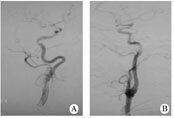

1.1對(duì)象2011-08至2012-02在我院住院的缺血性腦卒中患者,經(jīng)腦血管造影篩選出年滿18周歲、頸內(nèi)動(dòng)脈迂曲(頸內(nèi)動(dòng)脈彎曲如螺旋狀或有2個(gè)或2個(gè)以上的彎曲)、而無狹窄或閉塞的患者30例(迂曲組,圖1A),無頸內(nèi)動(dòng)脈迂曲、狹窄或閉塞的患者30例(無迂曲組,圖1B)。所有患者在腦血管造影前均簽署手術(shù)知情同意書。

圖1患者頸內(nèi)動(dòng)脈血管造影

A迂曲;B無迂曲